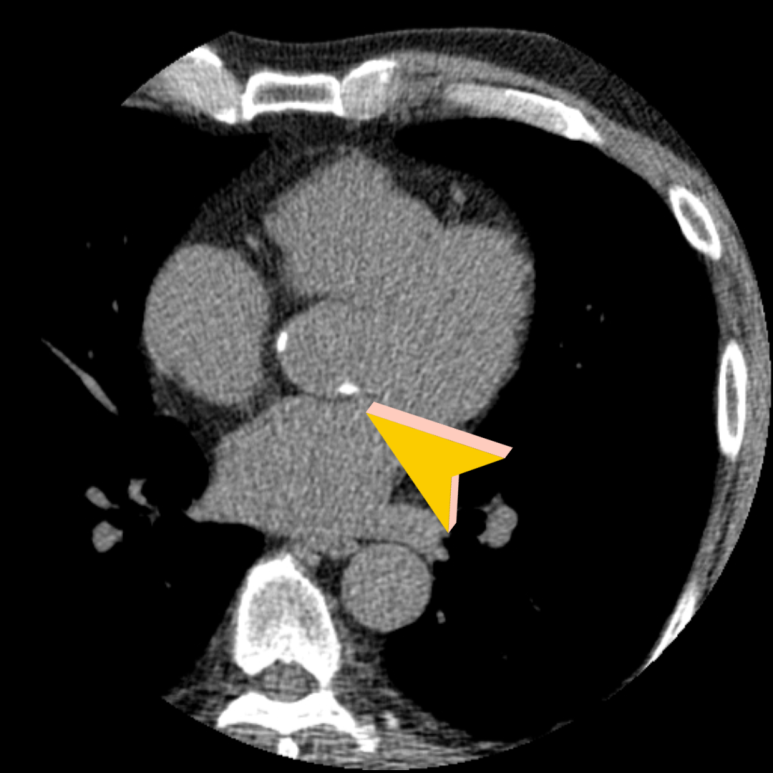

• 상행 대동맥 석회화 상행 대동맥 석회화

• 하행 대동맥 석회화 하행 대동맥 석회화